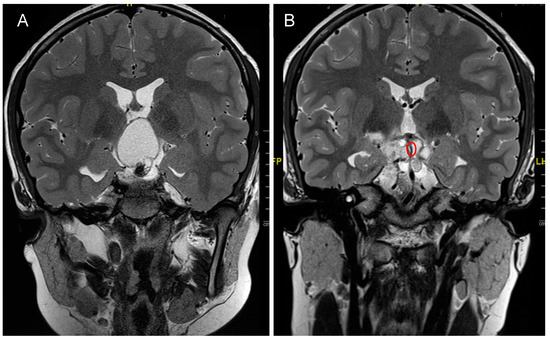

4. Craniopharyngioma

4.1. Incidence and Classification

4.2. Clinical Presentation

4.3. Treatment Strategies and Outcome